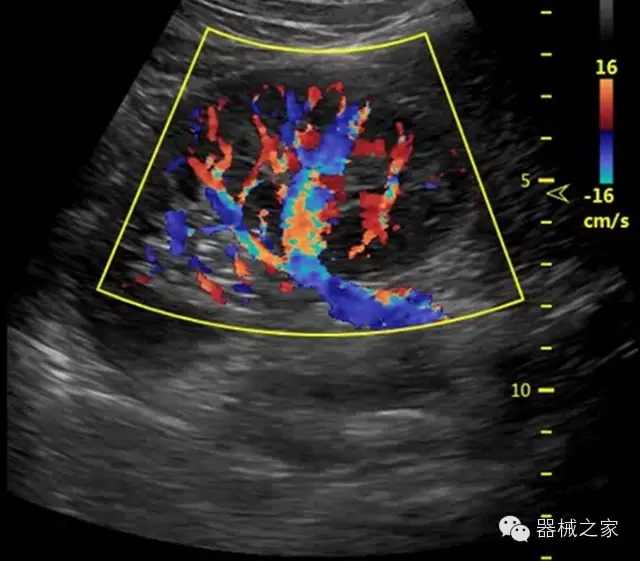

臨床圖片賞析

產(chǎn)品特點

·獨有的RF平臺提高微小細(xì)節(jié)顯示、圖像對比度和邊界清晰度;

·特有的XCEN探頭,超寬的帶寬,表現(xiàn)更高分辨率和對比度;

·單晶純凈波探頭提供更佳的穿透力和彩色敏感度;

·獨有RF敏感血流使得心臟血流完美呈現(xiàn);